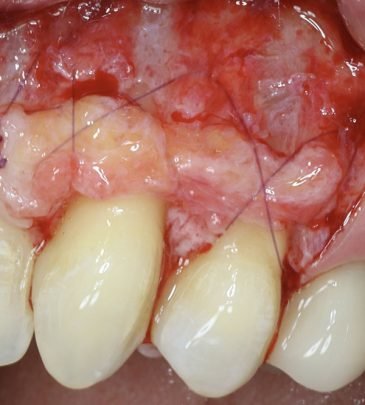

Our team of reputed dental practitioners is committed to ensuring that our courses are relevant, engaging, and reflect the latest advances in dentistry. Our wealth of clinical experience is leveraged through the collaborative effort in teaching fundamental concepts to advanced procedures in restorative dentistry, implantology, orthodontics, and periodontics.